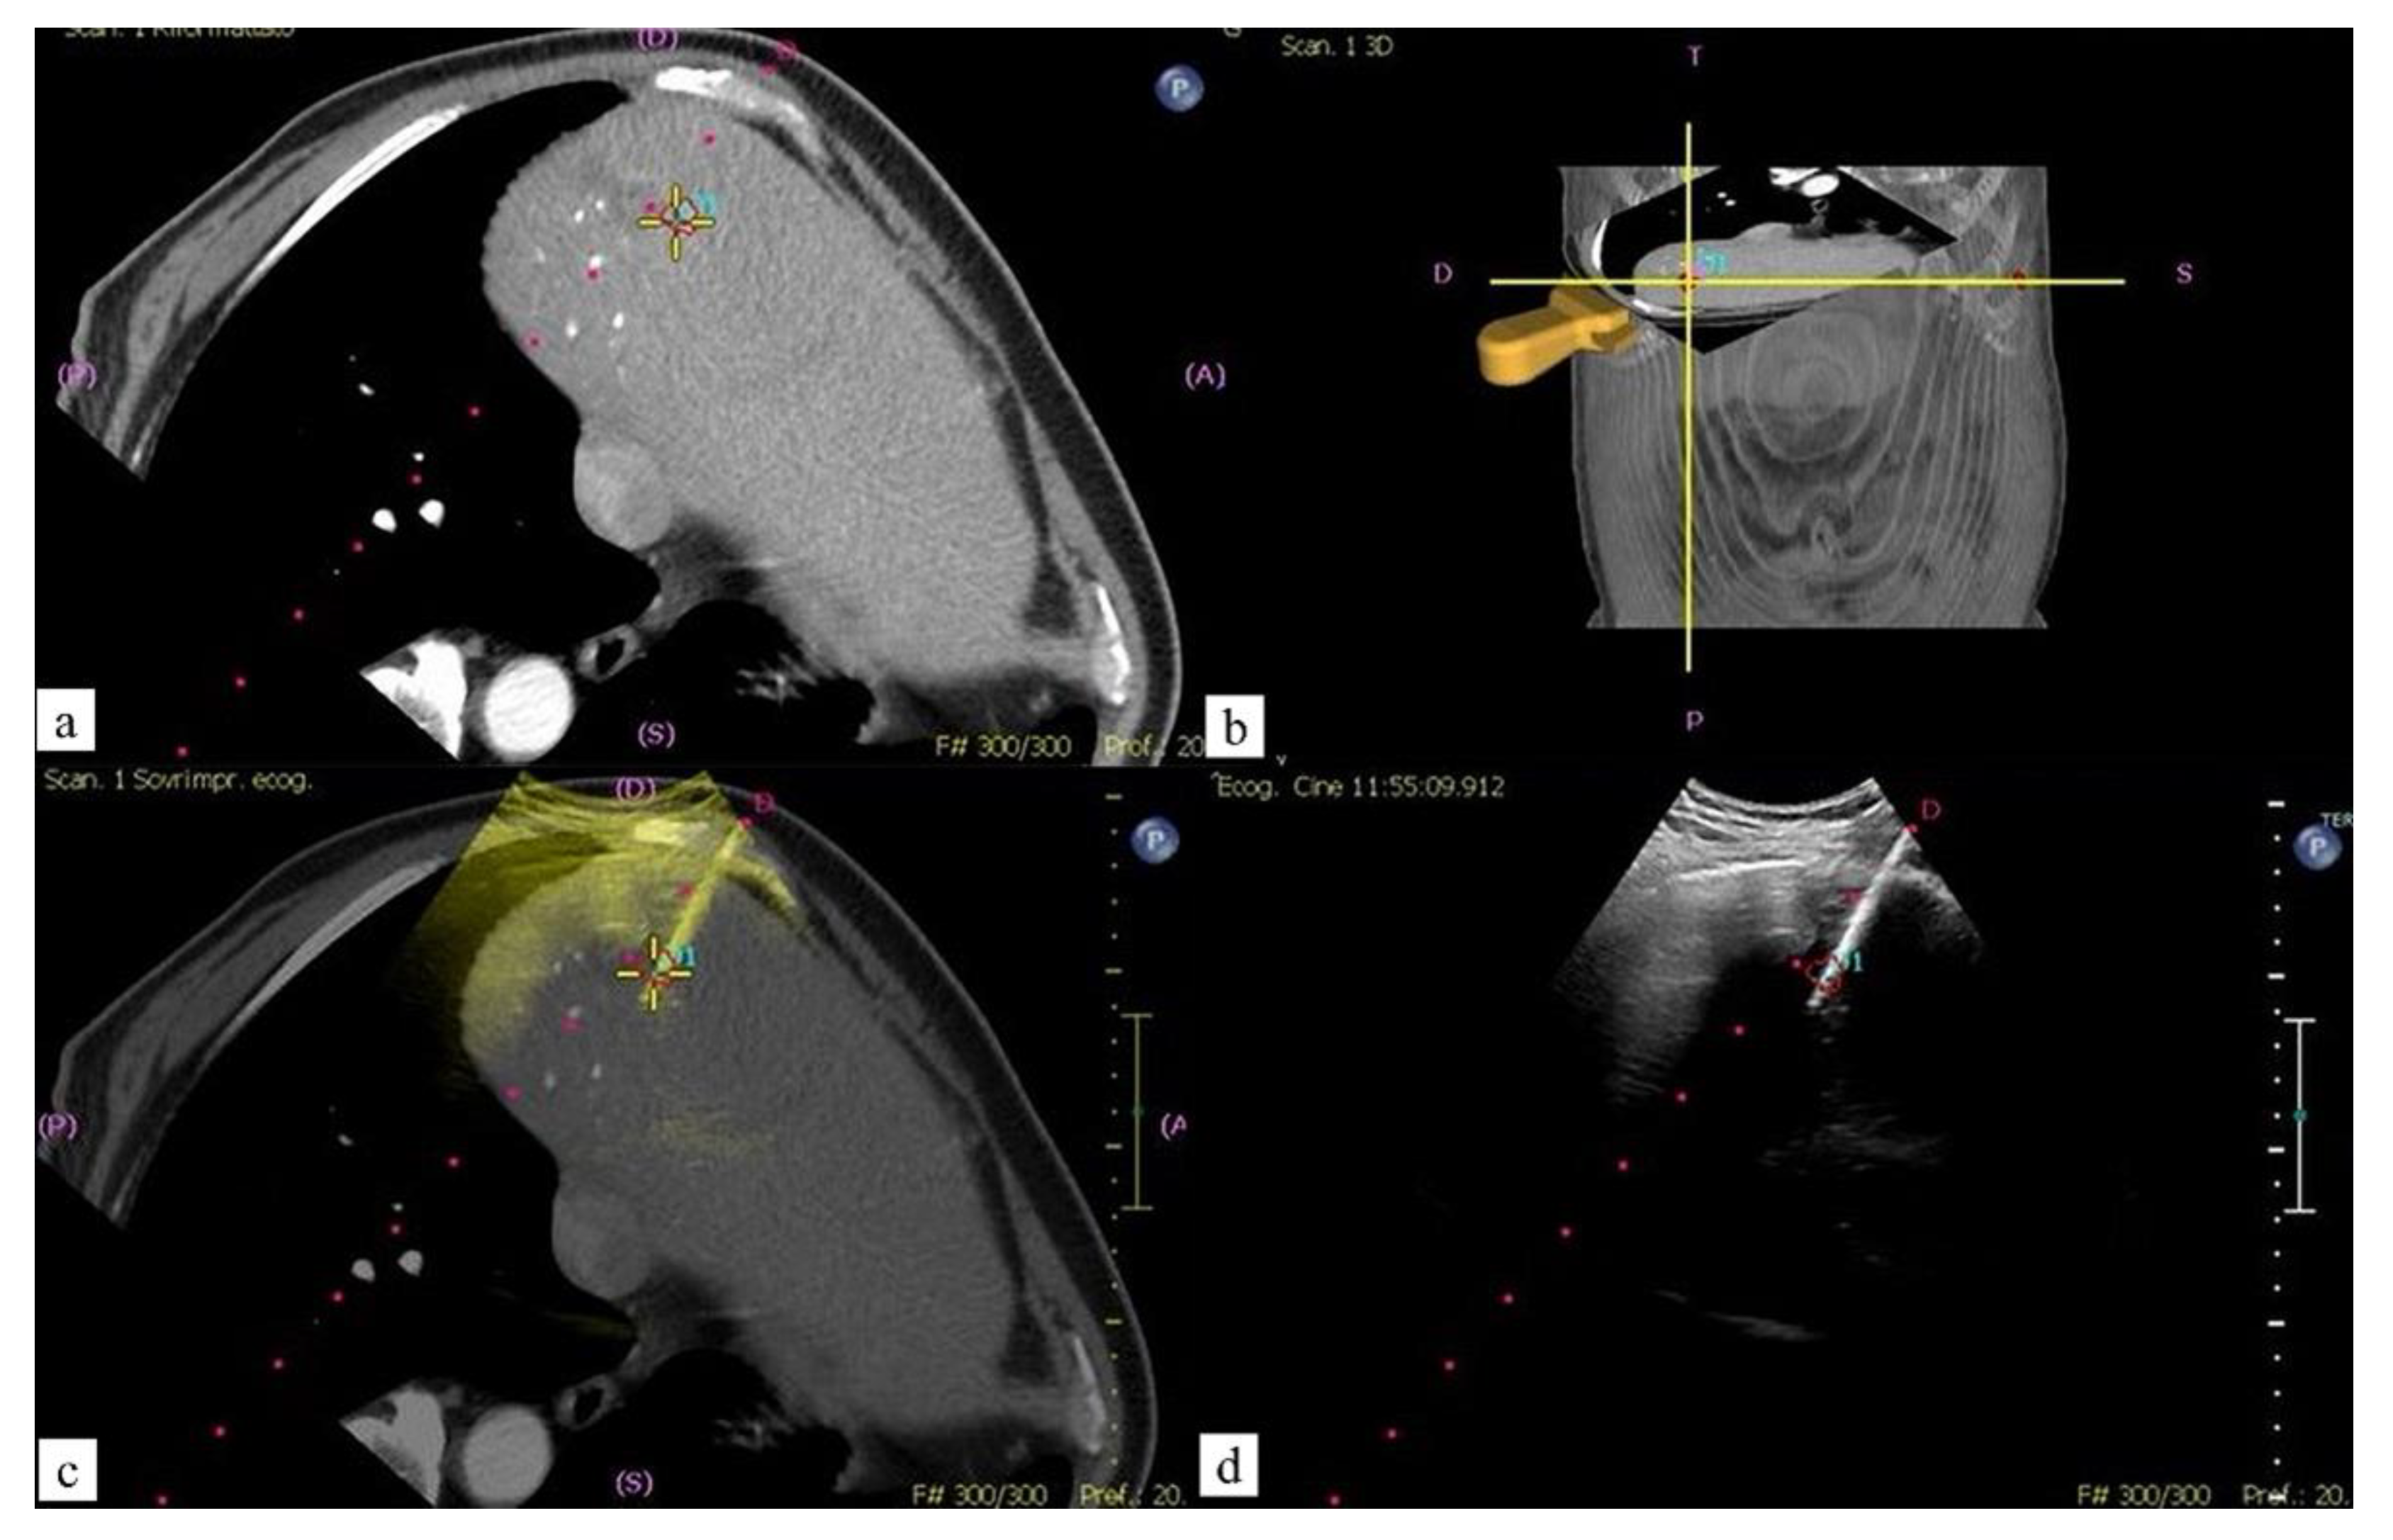

- Carriero, S.; Della Pepa, G.; Monfardini, L.; Vitale, R.; Rossi, D.; Masperi, A.; Mauri, G. Role of Fusion Imaging in Image-Guided Thermal Ablations. Diagnostics 2021, 11, 549. [Google Scholar] [CrossRef] [PubMed]

- Minami, Y.; Kudo, M. Ultrasound Fusion Imaging Technologies for Guidance in Ablation Therapy for Liver Cancer. J. Med. Ultrason. 2020, 47, 257–263. [Google Scholar] [CrossRef] [PubMed]

- Mauri, G.; Cova, L.; De Beni, S.; Ierace, T.; Tondolo, T.; Cerri, A.; Goldberg, S.N.; Solbiati, L. Real-Time US-CT/MRI Image Fusion for Guidance of Thermal Ablation of Liver Tumors Undetectable with US: Results in 295 Cases. Cardiovasc. Interv. Radiol. 2015, 38, 143–151. [Google Scholar] [CrossRef] [PubMed]

- Monfardini, L.; Orsi, F.; Caserta, R.; Sallemi, C.; Della Vigna, P.; Bonomo, G.; Varano, G.; Solbiati, L.; Mauri, G. Ultrasound and Cone Beam CT Fusion for Liver Ablation: Technical Note. Int. J. Hyperth. 2018, 35, 500–504. [Google Scholar] [CrossRef] [Green Version]